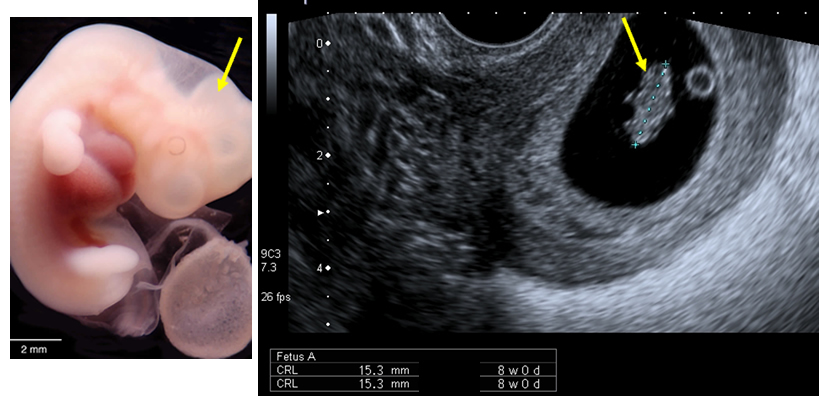

The embryo has grown by 5 mm, measuring the crown-rump length.

| Fig 1b Reproduced with kind permission from Brad Smith, University of Michigan; NICHHD: NO1 HD 6 3257 |